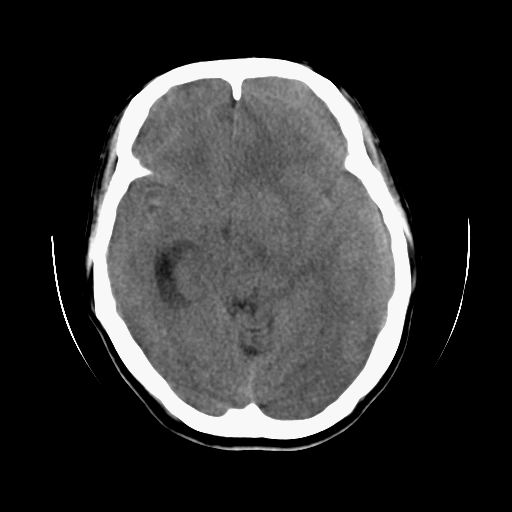

标题: CT13217:头部外伤三月余,头痛三天 [打印本页]

标题: CT13217:头部外伤三月余,头痛三天

左侧慢性硬膜下血肿

太典型,左侧慢性硬膜下血肿

左侧慢性硬膜下血肿,大脑镰下疝。

支持左额颞顶慢性硬膜下血肿伴大脑镰下疝。

血肿是急性、亚急性、还是慢性,要结合外伤时间考虑的,本例头部外伤三个月,应该是明显的慢性硬膜下血肿,但血肿的等密度显然不符合病理改变,估计是合并再次出血,中线结构移位明显,有脑疝形成。应穿刺减压。

血肿是急性、亚急性、还是慢性,要结合外伤时间考虑的,本例头部外伤三个月,应该是明显的慢性硬膜下血肿,但血肿的等密度显然不符合病理改变,估计是合并再次出血,中线结构移位明显,有脑疝形成。应穿刺减压。 大于2个月为慢性出血,2周到二个月为亚急性出血